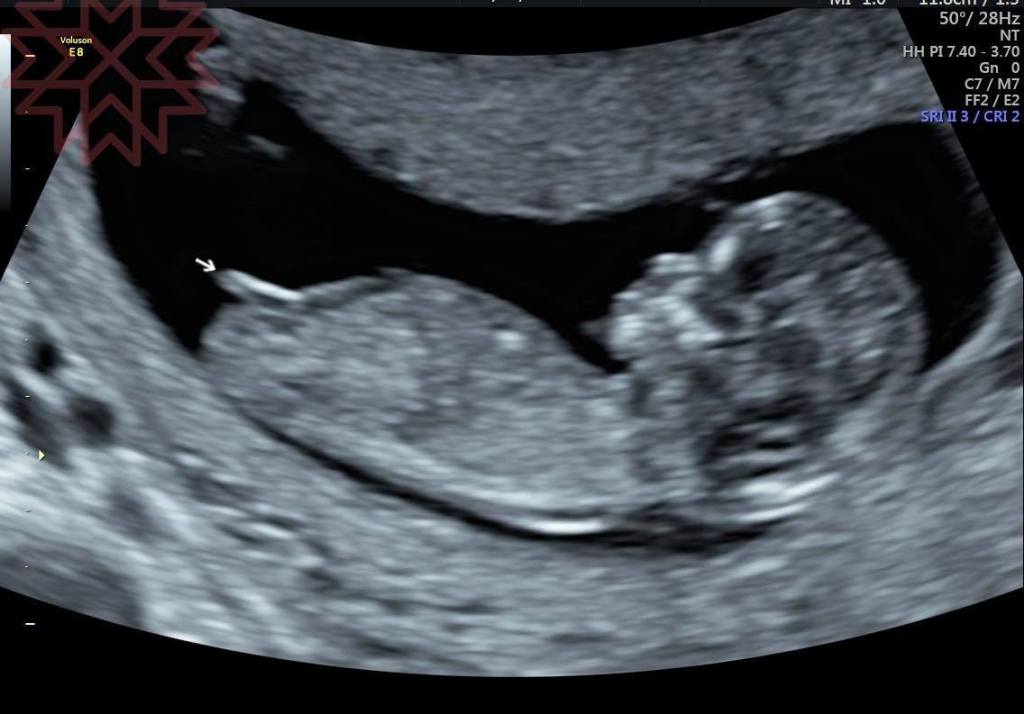

像這個情況

12週

用立體超音波真的不行啦

請看第三張圖

上面那一根1是臍帶

下面隱隱約約的那一根2叫做生殖結節![]()

所以真的要看就像我最後兩張圖我們可以用2D的超音波縱切面來去稍微做判斷

請看第一張圖

就是看角度

男寶寶角度比較大女寶寶角度比較小

最後兩張圖就給你猜猜哪個是男寶寶那個是女寶寶好了

正確率大概比用猜的50 %上升到八成左右有人會說到九成其實聽聽參考就好啦